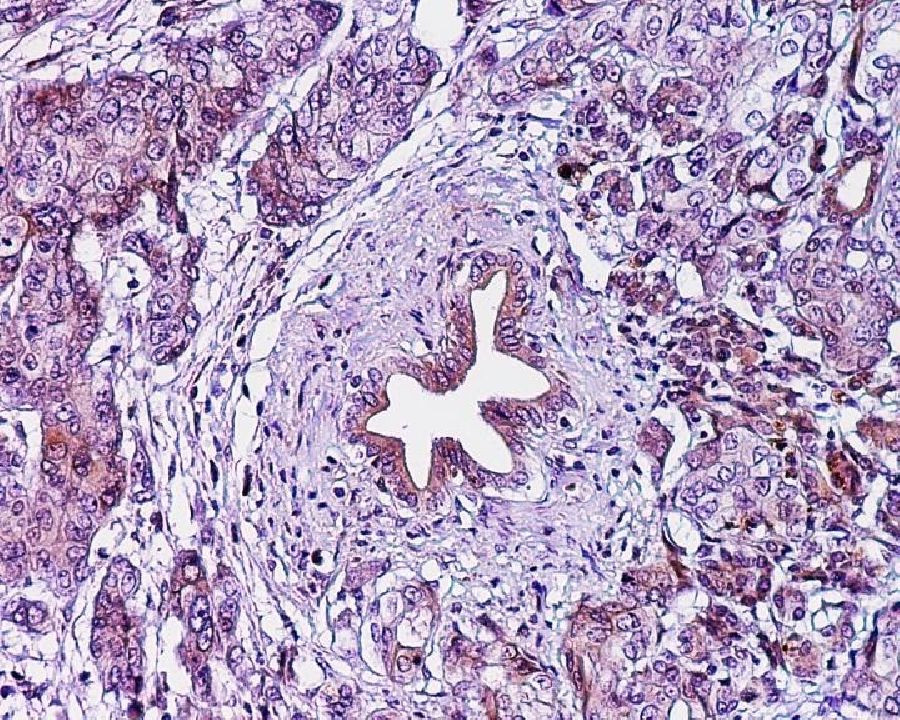

Si bien el objetivo de la resección es extirpar todo el tejido tumoral, puede ser difícil de lograr, especialmente si el cáncer se ha diseminado a los vasos sanguíneos cercanos que alimentan el hígado y el intestino delgado.

La cantidad de tejido canceroso que queda después de la cirugía en los bordes del área resecada es un predictor significativo de supervivencia después de la cirugía por cáncer de páncreas. Los pacientes que no tienen tejido canceroso después de la resección (R0) tienen una mejor supervivencia en comparación con los pacientes con cantidades microscópicas (R1) o macroscópicas (R2) de tejido canceroso que quedan después de la resección. Este estudio analizó los resultados de la resección R1 y R2 en comparación con la quimioterapia sola.